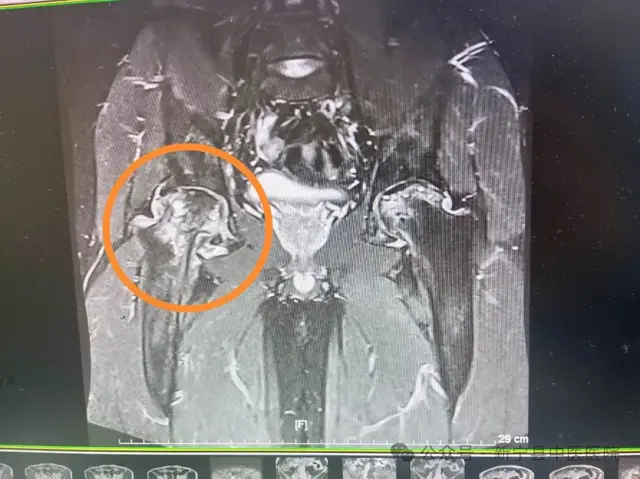

这位男性患者今年55岁 , 主要的困扰就是 , 身上老是莫名其妙青一块儿 , 紫一块儿 , 而且保持一个姿势半个小时就会感觉肩背僵硬 , 伴有酸痛感 , 胸部憋闷 , 爬两层楼梯都要停下来歇五分钟 , 偶尔身上会有肿块 , 一按就刺痛难忍 。 西医 , 中医都试过 , 血府逐瘀芄 , 活络效灵丹也都吃过 , 基本上管不了多长时间 , 过一阵血瘀又卷土重来 。